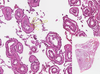

Testicular Atrophy Flashcards

Testicular Atrophy

Expanded Interstitium

Fibrous Envelope

Hyalinised Tubule —- Leydig Cells

Leydig Cells

Proliferated Leydig Cells

Sertoli Cells

Tubule with Spermatogonia and Primary Spermatocytes

Tubules with Germinative Epithelium

Tubules with thicker basement membranes